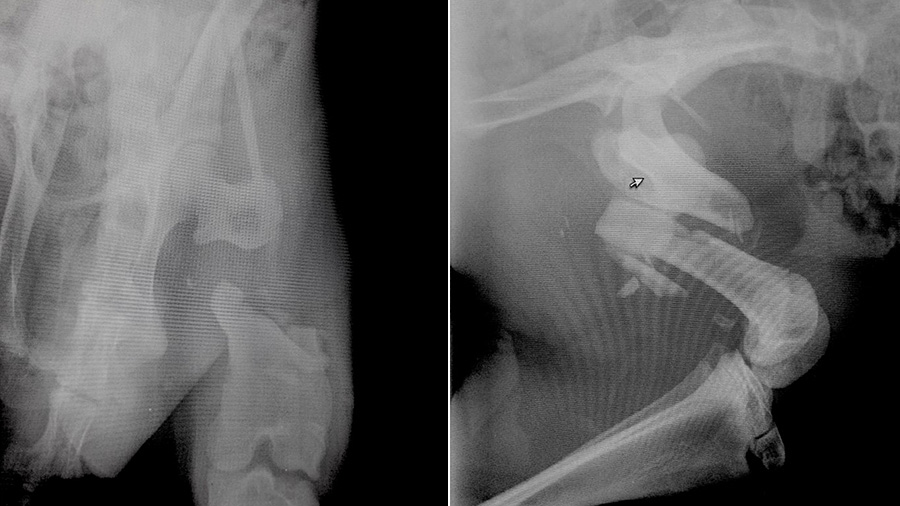

“This young kangaroo had just been acquired by a safari adventure park in Italy and the park’s veterinarian sent it to the hospital where I was working in 2015. The poor thing suffered from a comminuted fracture of the femoral shaft extending from the subtrochanteric region to the distal femur,” he explained. “The park owner wasn’t too convinced to let us try to fix the patient because he was told there was no way to successfully treat the fracture. But I was keen to do something about it and Matteo, the park’s vet, was very convincing with the owner. The hospital staff could not stop taking pictures as the patient was like a big, funny mouse!”

The challenges were many and they had to be taken seriously. First, there was no time to find sources of anatomical reference for red kangaroos in the medical literature. Surely, they existed with an accurate search, but the clock was ticking. Second, anesthetizing a kangaroo is not a straightforward procedure, a factor that had to be taken seriously as a mistake could have jeopardized the patient’s life or resulted in serious harm to the surgical team, given the animal’s powerful and potentially lethal hind quarters.

“I knew I could fix the bone but I was concerned because I could not gather enough information regarding the approach. I did a quick Internet search but I found no references in the literature and this fracture needed to be fixed as soon as possible, considering the huge muscles involved and the possibility for dramatic contracture that would have made the reduction impossible or even a compartment syndrome,” he said.

Using an intramedullary pin associated with double locking plates (rod and plate configuration) the fracture was bridged without an attempt to achieve perfect anatomic reduction but just focusing on the correct alignment.

“I had to identify similarities of anatomical structures. Some were different from what I was expecting. For example, the shape of the biceps femoris was deceiving and was converging toward what I expected to be the patella,” he said. “I discovered that the kangaroo doesn’t have a patella! I had to place the implant in a position that would not interfere with other anatomical structures, so I placed it as distally as I could. The realignment had to be perfect and the fixation super strong in order to allow the patient to bear weight on the hind limbs as soon as he was awake.”